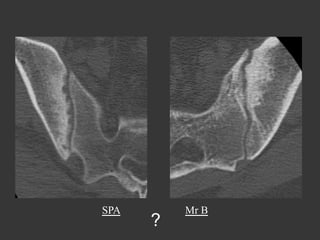

Mr B., 20 years old

Inflammatory Low back pain

?

SPA

Mr B